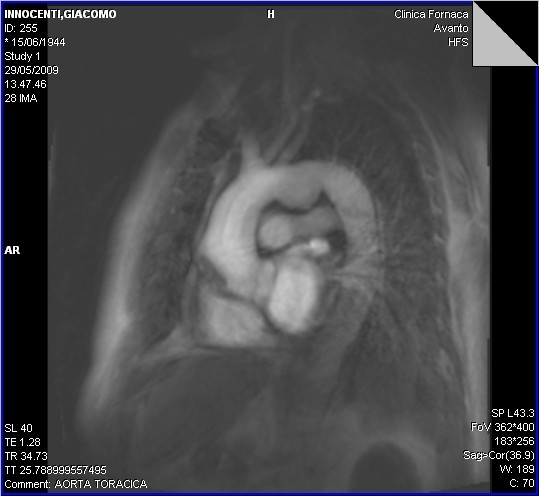

coronaro TC